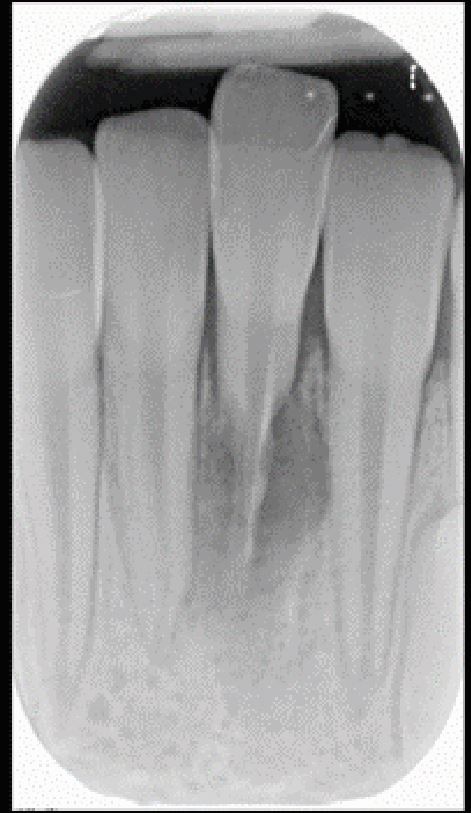

Patients and, in the case of minors, their advocates, must be made aware of potential TDI sequelae, the need for follow-up and problematic signs/symptoms to look out for. Figure 1 illustrates a case example where the patient failed to return for review and at four months post injury, a hopeless outlook for the previously traumatised tooth evident. Although earlier attendance may not have changed the outlook in this case, it is essential patients understand the importance of TDI follow-up as early intervention can improve some outcomes.

A consequence of TDI can be the premature loss of a tooth, such as an avulsed tooth not recovered at the time of injury, or a tooth subsequently becoming unrestorable, such as that seen in Figure 1. Premature tooth loss must be factored into treatment planning. The patient age, tooth eruption stage and occlusion will require consideration, along with potential specialist referral. In most cases, retaining teeth or a poor outlook and maintaining the space of teeth already lost due to TDI is recommended whilst treatment planning takes place.